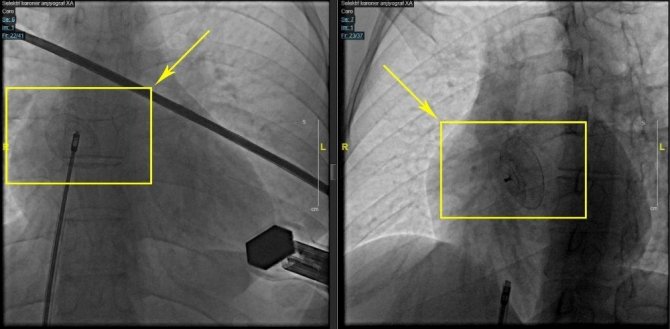

Nefes darlığı ve çarpıntı şikayetleriyle Manisa Şehir Hastanesi kardiyoloji polikliniğine başvuran genç hastanın kalbinde doğuştan bir delik olduğu tespit edildi. Yapılan ileri tetkikler sonucu kalp deliğinin açık kalp ameliyatına gerek kalmadan kapatılabileceği tespit edildi. Manisa Şehir Hastanesi anjiyografi ünitesinde 30 dakika süren işlem ile kalp deliği kapatılan hasta sağlığına kavuştu.

Ameliyatsız (perkütan) ASD kapama yönteminin anjiyodan bir farkı olmadığını kaydeden kardiyoloji doktorları cerrahi yöntemlere göre uygulamanın avantajları olduğunu kaydetti. ASD kapama yönteminde tedavi başarısının açık ameliyatlar kadar yüksek olduğuna dikkat çeken uzmanlar, komplikasyonların ise cerrahiye göre daha düşük olduğunu belirtti. Yapılan uygulama ile hastaların kısa süre hastanede kaldıklarını ve taburcu olduklarını kaydeden uzmanlar, taburcu olan hastaların günlük hayatlarına sorunsuz bir şekilde devam edebildiklerini söyledi.